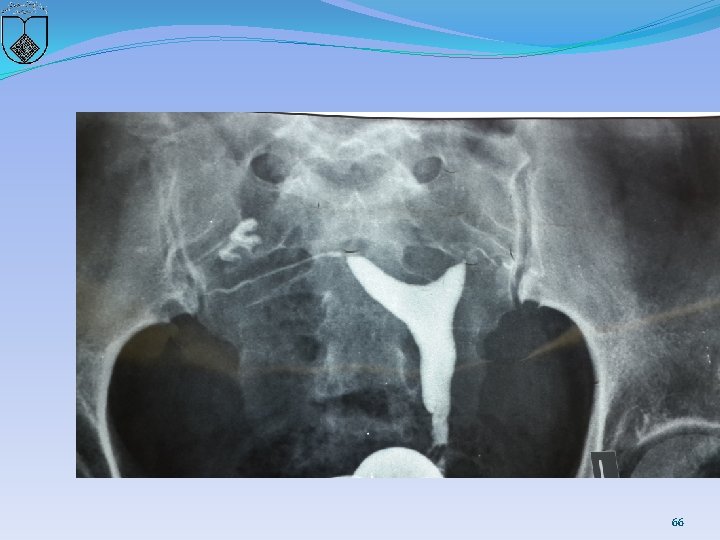

�ARE SEPTUM CHARACTERISTICS ASSOCIATED WITH WORSE REPRODUCTIVE OUTCOMES? �There is insufficient evidence to conclude that obstetric outcomes are different when comparing the size as defined by length or width of uterine septa. (Grade C) 65

66